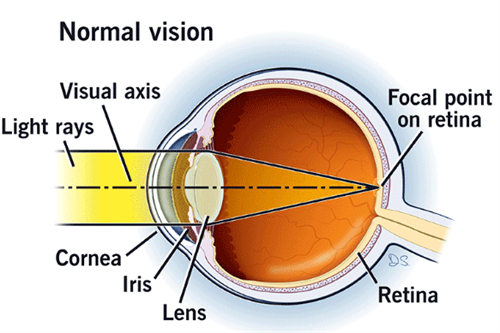

手术通常在局部或全身麻醉下进行,医生会在巩膜处制作微小切口,插入显微手术器械。

首可靠行玻璃体切除,清除眼内玻璃体以提供清晰视野;随后使用特定染色剂(如亮蓝)使黄斑前膜显色,便于比较准操作。

在显微镜下,医生用精细工具(如视网膜钩或镊子)小心抓住并剥离前膜,尽量减少对视网膜的损伤。

剥除后,详细检查视网膜表面是否有残留膜,并清理干净。然后,向眼内注入平衡盐溶液维持眼球形状,闭合切口。